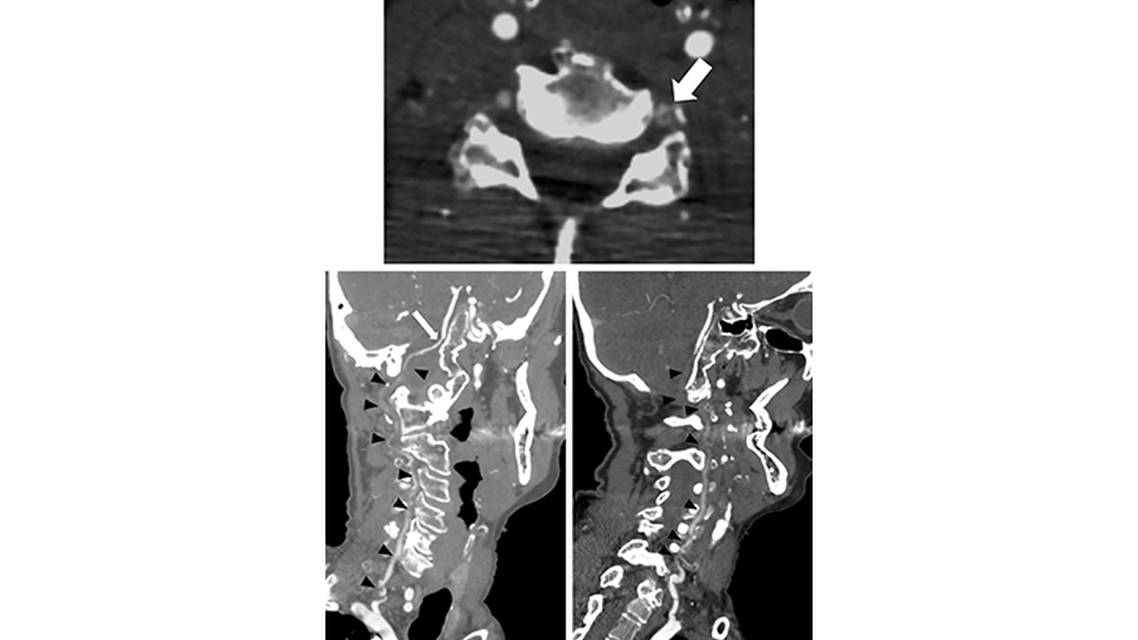

Noncontrast head CT revealed a subtle area of hypodensities in the bilateral cerebellar hemispheres. CT angiogram of the brain and neck showed extensive extracranial thrombus with multifocal severe stenosis or occlusion from the origin of the bilateral vertebral arteries to the vertebrobasilar junction, but a patent basilar artery (Figure 1). The right posterior inferior cerebellar artery (PICA) had likely retrograde filling; the left PICA was not seen. CT perfusion imaging revealed elevated time-to-maximum on RapidAI software (iSchemaView; Menlo Park, CA) in the bilateral cerebellar hemispheres with relatively preserved cerebral blood flow (Figure 2).